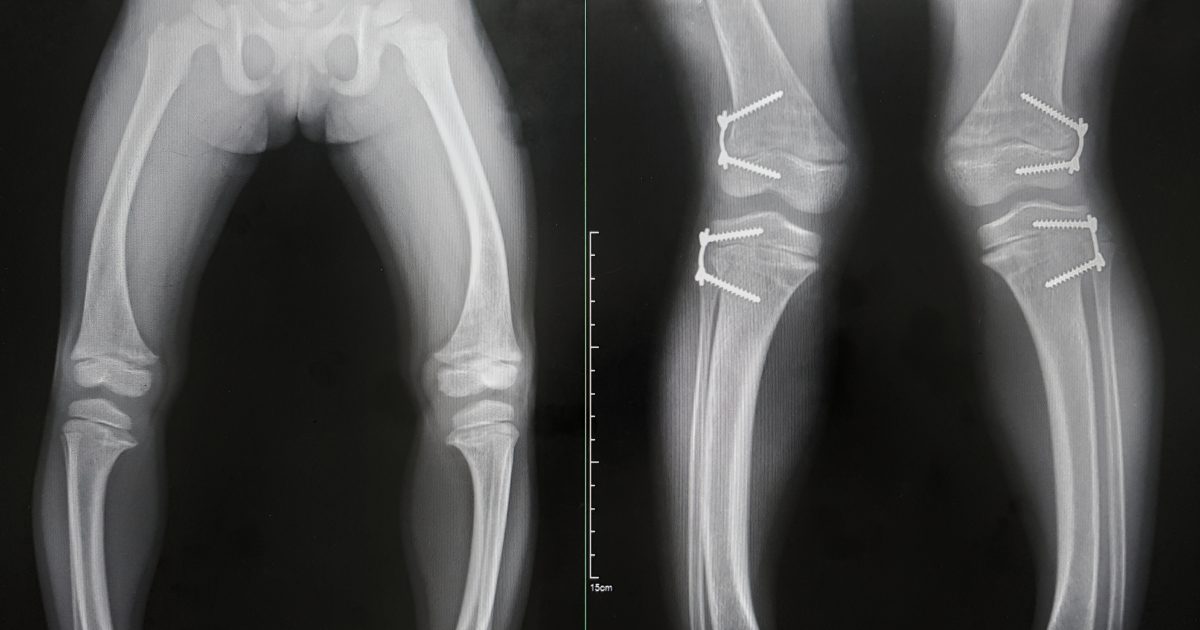

Die x-chromosomale Hypophosphatämie (kurz XLH) ist eine seltene Störung des Knochenstoffwechsels. Die Mutation, … Continued - „Ich bin wie alle!“ – Leben mit dem Alagille-Syndrom

Die x-chromosomale Hypophosphatämie (kurz XLH) ist eine seltene Störung des Knochenstoffwechsels, die durch … Continued - „Bei Seltenen Erkrankungen ist detektivischer Spürsinn gefragt“

Die x-chromosomale Hypophosphatämie (kurz XLH) ist eine seltene genetisch bedingte Störung des Knochenstoffwechsels, die zu einem chronischen Phosphatmangel führt. Wir sprachen mit dem Experten Priv.-Doz. Dr. Lothar Seefried über die Herausforderungen bei der Diagnose und Versorgung Betroffener. - Tenosynoviale Riesenzelltumore (TGCT): Gutartig, aber keinesfalls harmlos

Die x-chromosomale Hypophosphatämie (kurz XLH) ist eine seltene Störung des Knochenstoffwechsels, die durch … Continued - „Die Behandlung der Mastozytose war noch nie so wirksam möglich wie heute“

Die x-chromosomale Hypophosphatämie (kurz XLH) ist eine seltene Störung des Knochenstoffwechsels. Die Mutation, … Continued - Morbus Fabry und Morbus Pompe – „Die Lebensqualität der Betroffenen steht immer im Vordergrund“

Die x-chromosomale Hypophosphatämie (kurz XLH) ist eine seltene Störung des Knochenstoffwechsels, die durch … Continued - Paramyotonie: Vom Leben in der Dauerpause zum Leben mit Pausen